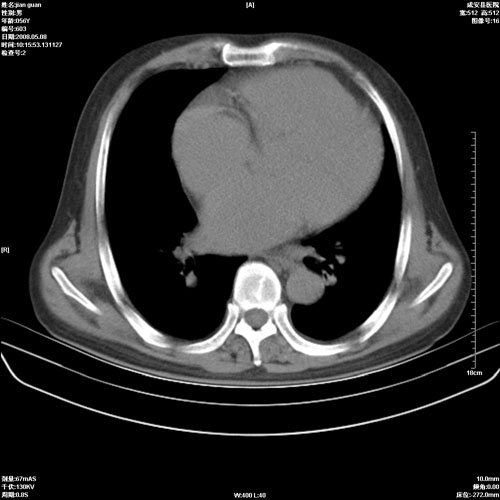

病人 男 60岁 主诉 胸闷 无明显发热 一般情况尚可。

考虑1心功不全,肺水肿

2.心脏增大(以左心室增大为著),请结合b超及听诊.

2.肺门血管扩张,心脏增大,为肺心病

3.肺心病.

陈旧性肺结核,左心房扩大,左心衰竭

2右上肺结核纤维性病灶、肺气肿 ,肺心病